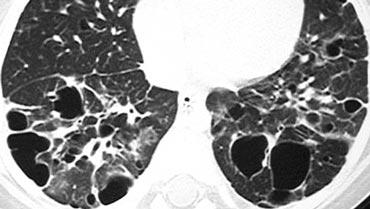

Ca lâm sàng minh họa: Protein phế nang

Hình ảnh: Bệnh nhân có dày vách liên tiểu thùy kết hợp mờ kính mờ dạng đốm. Một số tiểu thùy bị tổn thương trong khi các tiểu thùy khác được bảo tồn.

Sự kết hợp này được gọi là “crazy-paving” (dạng lát đá không đều).

Dấu hiệu Crazy-Paving:

- Ban đầu được coi là đặc hiệu cho protein phế nang, nhưng hiện nay được ghi nhận trong nhiều bệnh lý, bao gồm:

- Viêm phổi do Pneumocystis jirovecii

- Ung thư biểu mô phế quản-phế nang

- Sarcoidosis

- Viêm phổi kẽ không đặc hiệu (NSIP)

- Viêm phổi tổ chức hóa (COP)

- Hội chứng suy hô hấp cấp tính ở người lớn (ARDS)

- Xuất huyết phổi

Protein phế nang:

- Một bệnh phổi lan tỏa hiếm gặp, chưa rõ nguyên nhân.

- Đặc trưng bởi sự tích tụ trong phế nang và mô kẽ của chất phospholipo-protein dương tính với phản ứng acid periodic-Schiff (PAS), có nguồn gốc từ surfactant.